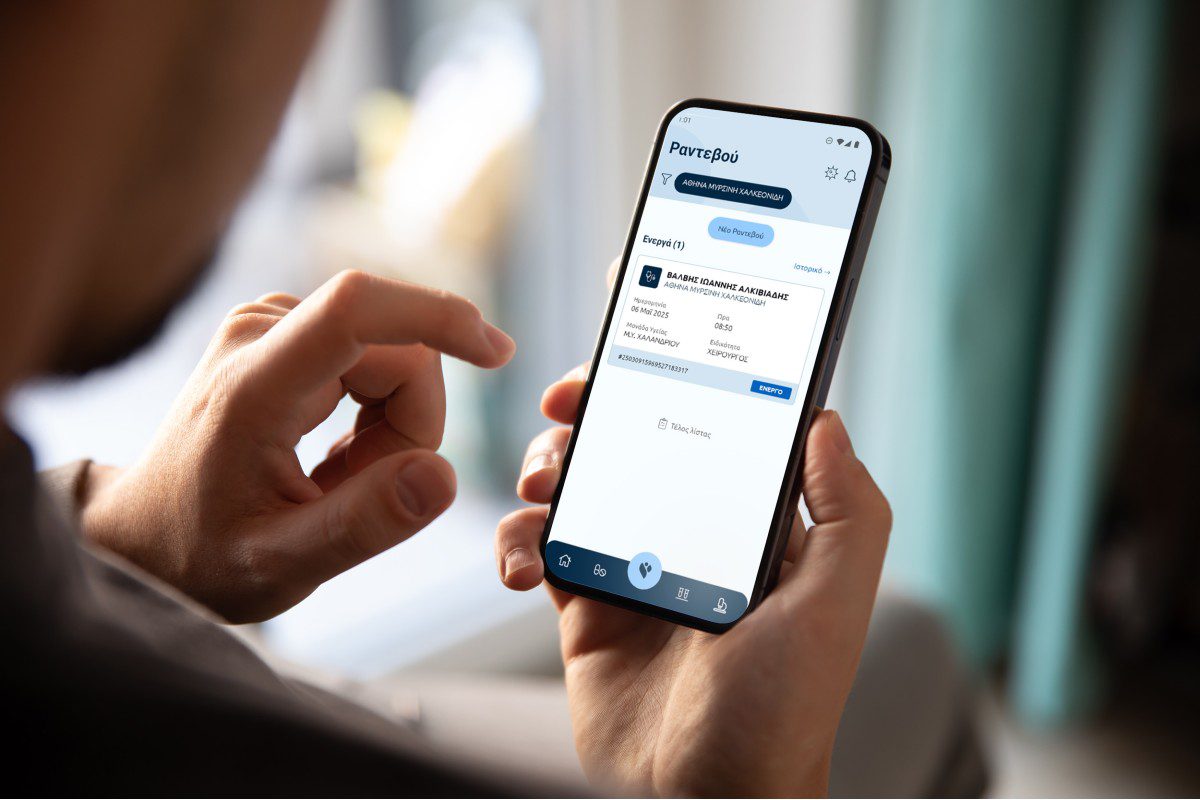

Πρόκειται για τη νέα ψηφιακή πλατφόρμα του Εθνικού Συστήματος Υγείας, μέσω της οποίας οι πολίτες αποκτούν άμεση και εύκολη πρόσβαση στο ιατρικό τους ιστορικό, και οι ιατροί έχουν στη διάθεσή τους συγκεντρωμένα τα κλινικά δεδομένα των ασθενών. Η πλατφόρμα συγκεντρώνει, για πρώτη φορά σε ένα σημείο, πληροφορίες υγειονομικού προφίλ από όλες τις μονάδες και τις βαθμίδες υγείας, δημόσιου και ιδιωτικού τομέα. Η πρόσβαση στον ΕΗΦΥ πραγματοποιείται μέσω των εφαρμογών myHealth για τους πολίτες, από κινητό ή υπολογιστή, και myHealthDoc για τους γιατρούς, από υπολογιστή και σύντομα και από κινητό.

Η αναβαθμισμένη εφαρμογή myHealth επιτρέπει στον πολίτη να βλέπει τις διαγνώσεις, τις συνταγές φαρμάκων, τα παραπεμπτικά, αλλά και τα αποτελέσματα των εξετάσεων, τα δεδομένα από μητρώα ασθενειών, τις νοσηλείες, τις ιατρικές βεβαιώσεις, τα εμβόλια, τις αλλεργίες και να προγραμματίζει τα ραντεβού του με γιατρούς, εύκολα και γρήγορα. Επιπλέον, οι γονείς αποκτούν πρόσβαση στο ιατρικό ιστορικό των έμμεσων ασφαλισμένων μελών της οικογένειας, δηλ. των ανήλικων παιδιών. Η εφαρμογή είναι διαθέσιμη δωρεάν, για Αndroid και ΙΟS κινητές συσκευές, καθώς και για υπολογιστή στο: https://citizen.ehealthrecord.gov.gr. Ήδη, πάνω από 750.000 πολίτες έχουν “κατεβάσει” και χρησιμοποιούν το myHealth app.